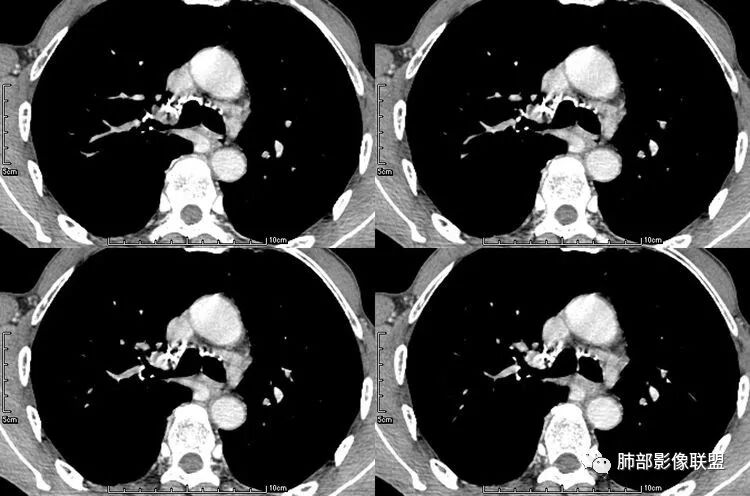

患者老年男性,咳嗽、咳痰、痰中带血伴胸闷2月余。长期大量吸烟史。查肝肾功能、血糖、血脂、心肌酶、电解质、血沉、C反应蛋白、抗“O”、类风湿因子、抗核抗体谱无明显异常。肿瘤标志物提示NSE、CYFRA21-1稍升高。胸部CT:肺气肿背景,左肺下叶后基底段不规则肿块影,见支气管截断,内见大片状低密度区及部分血管影,增强轻度强化,远端空洞形成。双肺多发不规则实性结节影、见毛刺、胸膜牵拉及血管集束,结节内见空洞形成,部分可见血管影,多位于胸膜下。双肺见多发肺大泡。综合考虑左下肺恶性病变并双肺转移。鳞癌或淋巴瘤可能。鉴别血管炎性病变及真菌感染。

张延军:双肺多发结节,空洞影,后者洞壁厚薄不均匀,部分腔内丝丝落落,呈分叶征,边缘见毛刺影,病灶大部分位于胸膜下,与血管相连,右肺下叶前基底段结节近段支气管截断,远端见空腔。左肺下叶病灶密度不均,背段支气管壁增厚,管腔狭窄。考虑1.双肺下叶占位性病变伴肺内空洞性转移 2.多原发的占位 3.肉芽肿性血管炎代排。

无发热,其他慢性细菌先不考虑,有的低毒的,但是结节形态还是比较不规则的,分布也是比较随机,更像原发病灶。真菌方面,结节没有融合,坏死也是液化坏死,不符合隐球菌,曲霉不符合IPA,慢性吸入的也少见。结核没有树丫,不考虑。鉴别主要是GPA,和肺癌。GPA不支持点是皮肤,肾脏没有累及,ANCA不支持。。。肺癌主要是腺癌和鳞癌转移。比较支持的是淋巴结肿大,和左下肺的主病灶,支气管堵塞和异常强化。还有分叶,局部膨隆。可以建议支气管镜检测。

大家按我提的单个病灶分析,很多提出来都是典型的腺癌

脐凹征、粗短毛刺、深分叶、中央结构杂乱

本病例左肺下叶肿块,有深分叶、毛刺、胸膜牵拉凹陷、支气管截断及纵隔内淋巴结肿大等征象,都均支持病灶为恶性,如腺癌,而且叶间裂的多发结节也提示是腺癌来源可能大;双肺多发结节、肿块,大部分病灶有分叶、毛刺及胸膜凹陷的恶性征象,与原发肿瘤本身的性质有关,所以应该与左肺下叶肿块同源,而且双肺多发病灶内空洞也具有多样性;